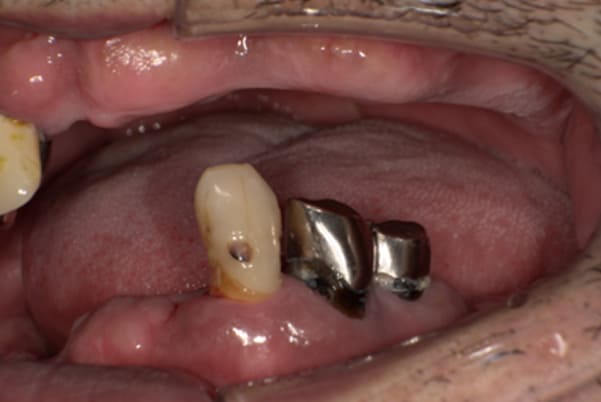

上の前歯が重度歯周病により動揺し、残せない状態のため、入れ歯も動揺がありました。

ご自身の歯に負担の少ないバネ、また見た目も改善

ご自身の歯に負担の少ないバネ

銀歯からセラミック歯に

バネをかける歯は繋げることで強度を増し、歯への負担を軽減し、歯の寿命を長くする設計へ。

バネがかかる歯の被せ物は、歯への負担を減らし、入れ歯が動きにくいようになる形態をあらかじめ付与することで、より入れ歯の機能が高まります。

治療を行う際、被せ物や入れ歯は、別々に考えるのではなく、一口腔単位としてお口全体のことを考え最良の治療計画を立てることが歯の寿命、機能効果を向上させるため、専門医としてこのことは常に心掛けて治療を行っています。